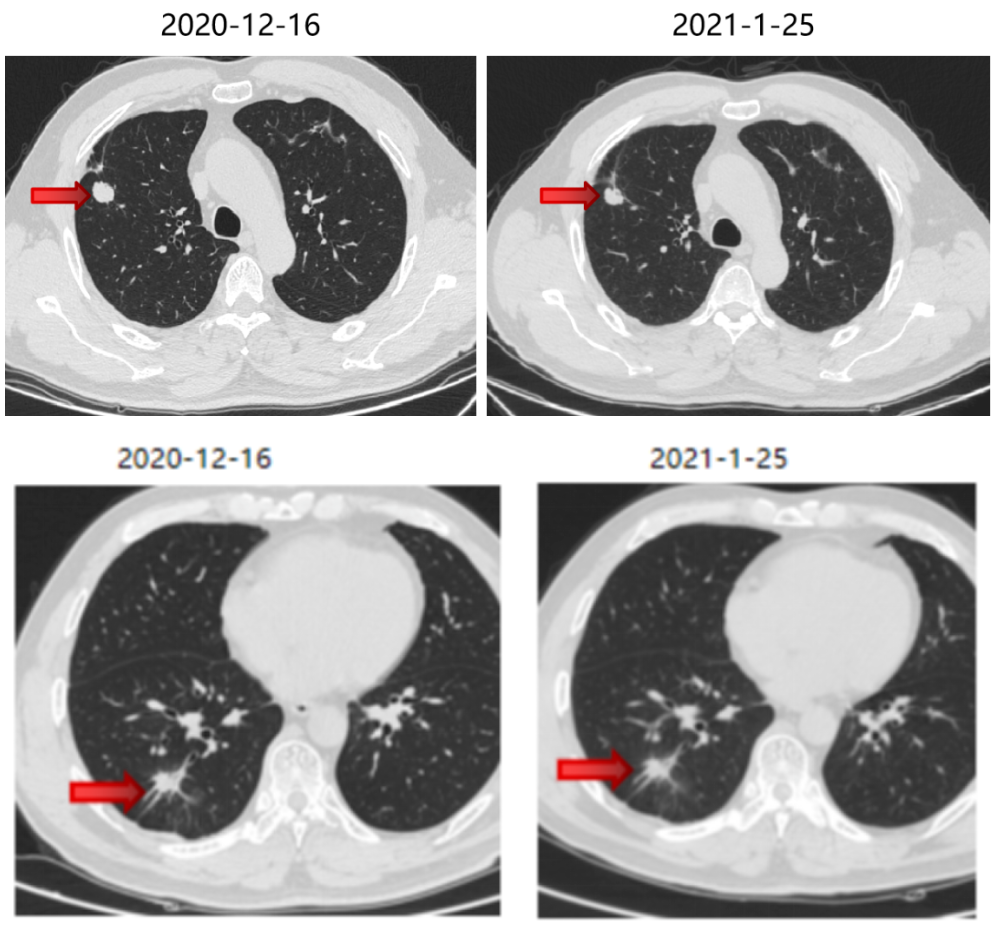

局部治疗(二):SBRT治疗

2020-11-6至2020-11-25 左肺下叶及右肺下叶转移灶放疗:95% PTV1-2 74.7Gy/4.98Gy/15F。

2020-12-31至2021-1-19右肺上叶转移灶放疗:95% PTV 74.7Gy/4.98Gy/15F。

SBRT疗效评价:部分缩小。

三线治疗

2021-1 起口服呋喹替尼3mg +曲妥珠单抗。

期间2021-3-15胸部CT:双肺转移瘤部分较前略增大,疗效SD。

三线治疗疗效评价:部分增大,PD。